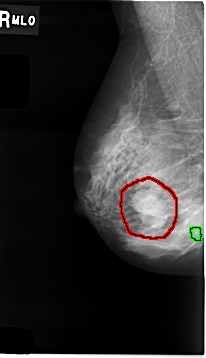

C_0008_1.RIGHT_MLO

RIGHT_MLO LINES 4648 PIXELS_PER_LINE 2672 BITS_PER_PIXEL 12 RESOLUTION 50 OVERLAY

FILE: C_0008_1.RIGHT_MLO.OVERLAY

TOTAL_ABNORMALITIES 2

ABNORMALITY 1

LESION_TYPE MASS SHAPE LOBULATED MARGINS MICROLOBULATED

ASSESSMENT 4

SUBTLETY 5

PATHOLOGY MALIGNANT

TOTAL_OUTLINES 1

BOUNDARY

ABNORMALITY 2

LESION_TYPE CALCIFICATION TYPE PUNCTATE DISTRIBUTION CLUSTERED

PATHOLOGY BENIGN